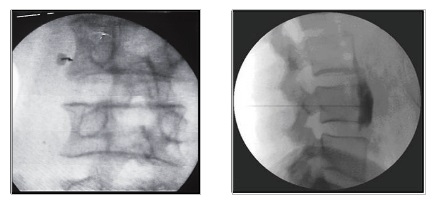

Πρόκειται για ελάχιστα επεμβατικές θεραπείες, οι οποίες εκτελούνται με διαδερμική προσπέλαση και ενδείκνυνται για τη θεραπεία του πόνου σε ασθενείς με οστεοπορωτικά και παθολογικά κατάγματα των σπονδύλων από μεταστατική καρκινική νόσο. Η κυφοπλαστική αποκαθιστά το ύψος του σπονδύλου με χρήση ειδικού μπαλονιού και εισαγωγή τσιμέντου, ενώ η σπονδυλοπλαστική αφορά σε απλή εισαγωγή τσιμέντου στον καταγματικό σπόνδυλο. Και οι δύο τεχνικές γίνονται μέσω ειδικών trocar που εισάγονται διαδερμικά υπό ακτινοσκοπικό έλεγχο στους αυχένες των σπονδύλων και προωθούνται στο σπονδυλικό σώμα, όπου γίνεται η έγχυση του τσιμέντου ταχείας πήξης. Το τσιμέντο σταθεροποιεί τον σπόνδυλο και αποτρέπει την ανάπτυξη κύφωσης στα πάσχοντα σημεία.

Η κυφοπλαστική επιλέγεται για πρόσφατα κατάγματα (έως 6 μηνών). Και οι δύο τεχνικές μπορούν να εφαρμοσθούν σε πολλά επίπεδα της σπονδυλικής στήλης. Έχουν μικρό ποσοστό επιπλοκών και προσφέρουν άμεση ανακούφιση από τον πόνο και ταχεία αποκατάσταση του ασθενούς. Χρειάζονται νοσηλεία μιας μέρας. Σε ασθενείς υψηλού κινδύνου γίνεται να ολοκληρωθούν με μέθη και όχι γενική αναισθησία.